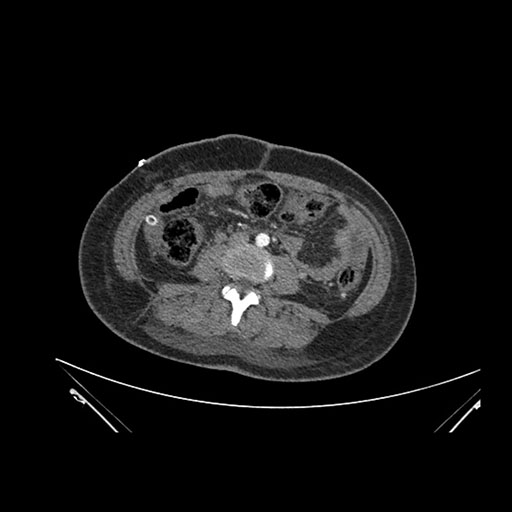

Imaging Analysis

Look through the patient's CT scan to identify any areas of concern for the necessary procedure.

Based on initial findings, which issue(s) would you be most concerned about?